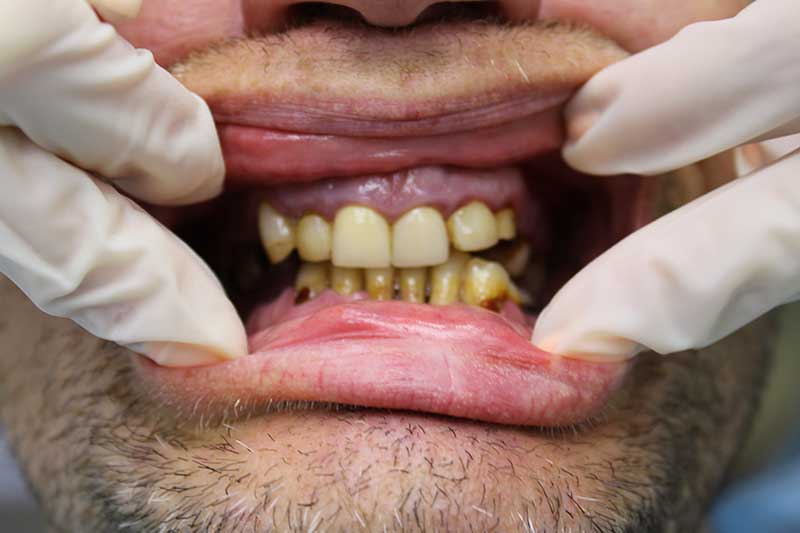

До имплантации